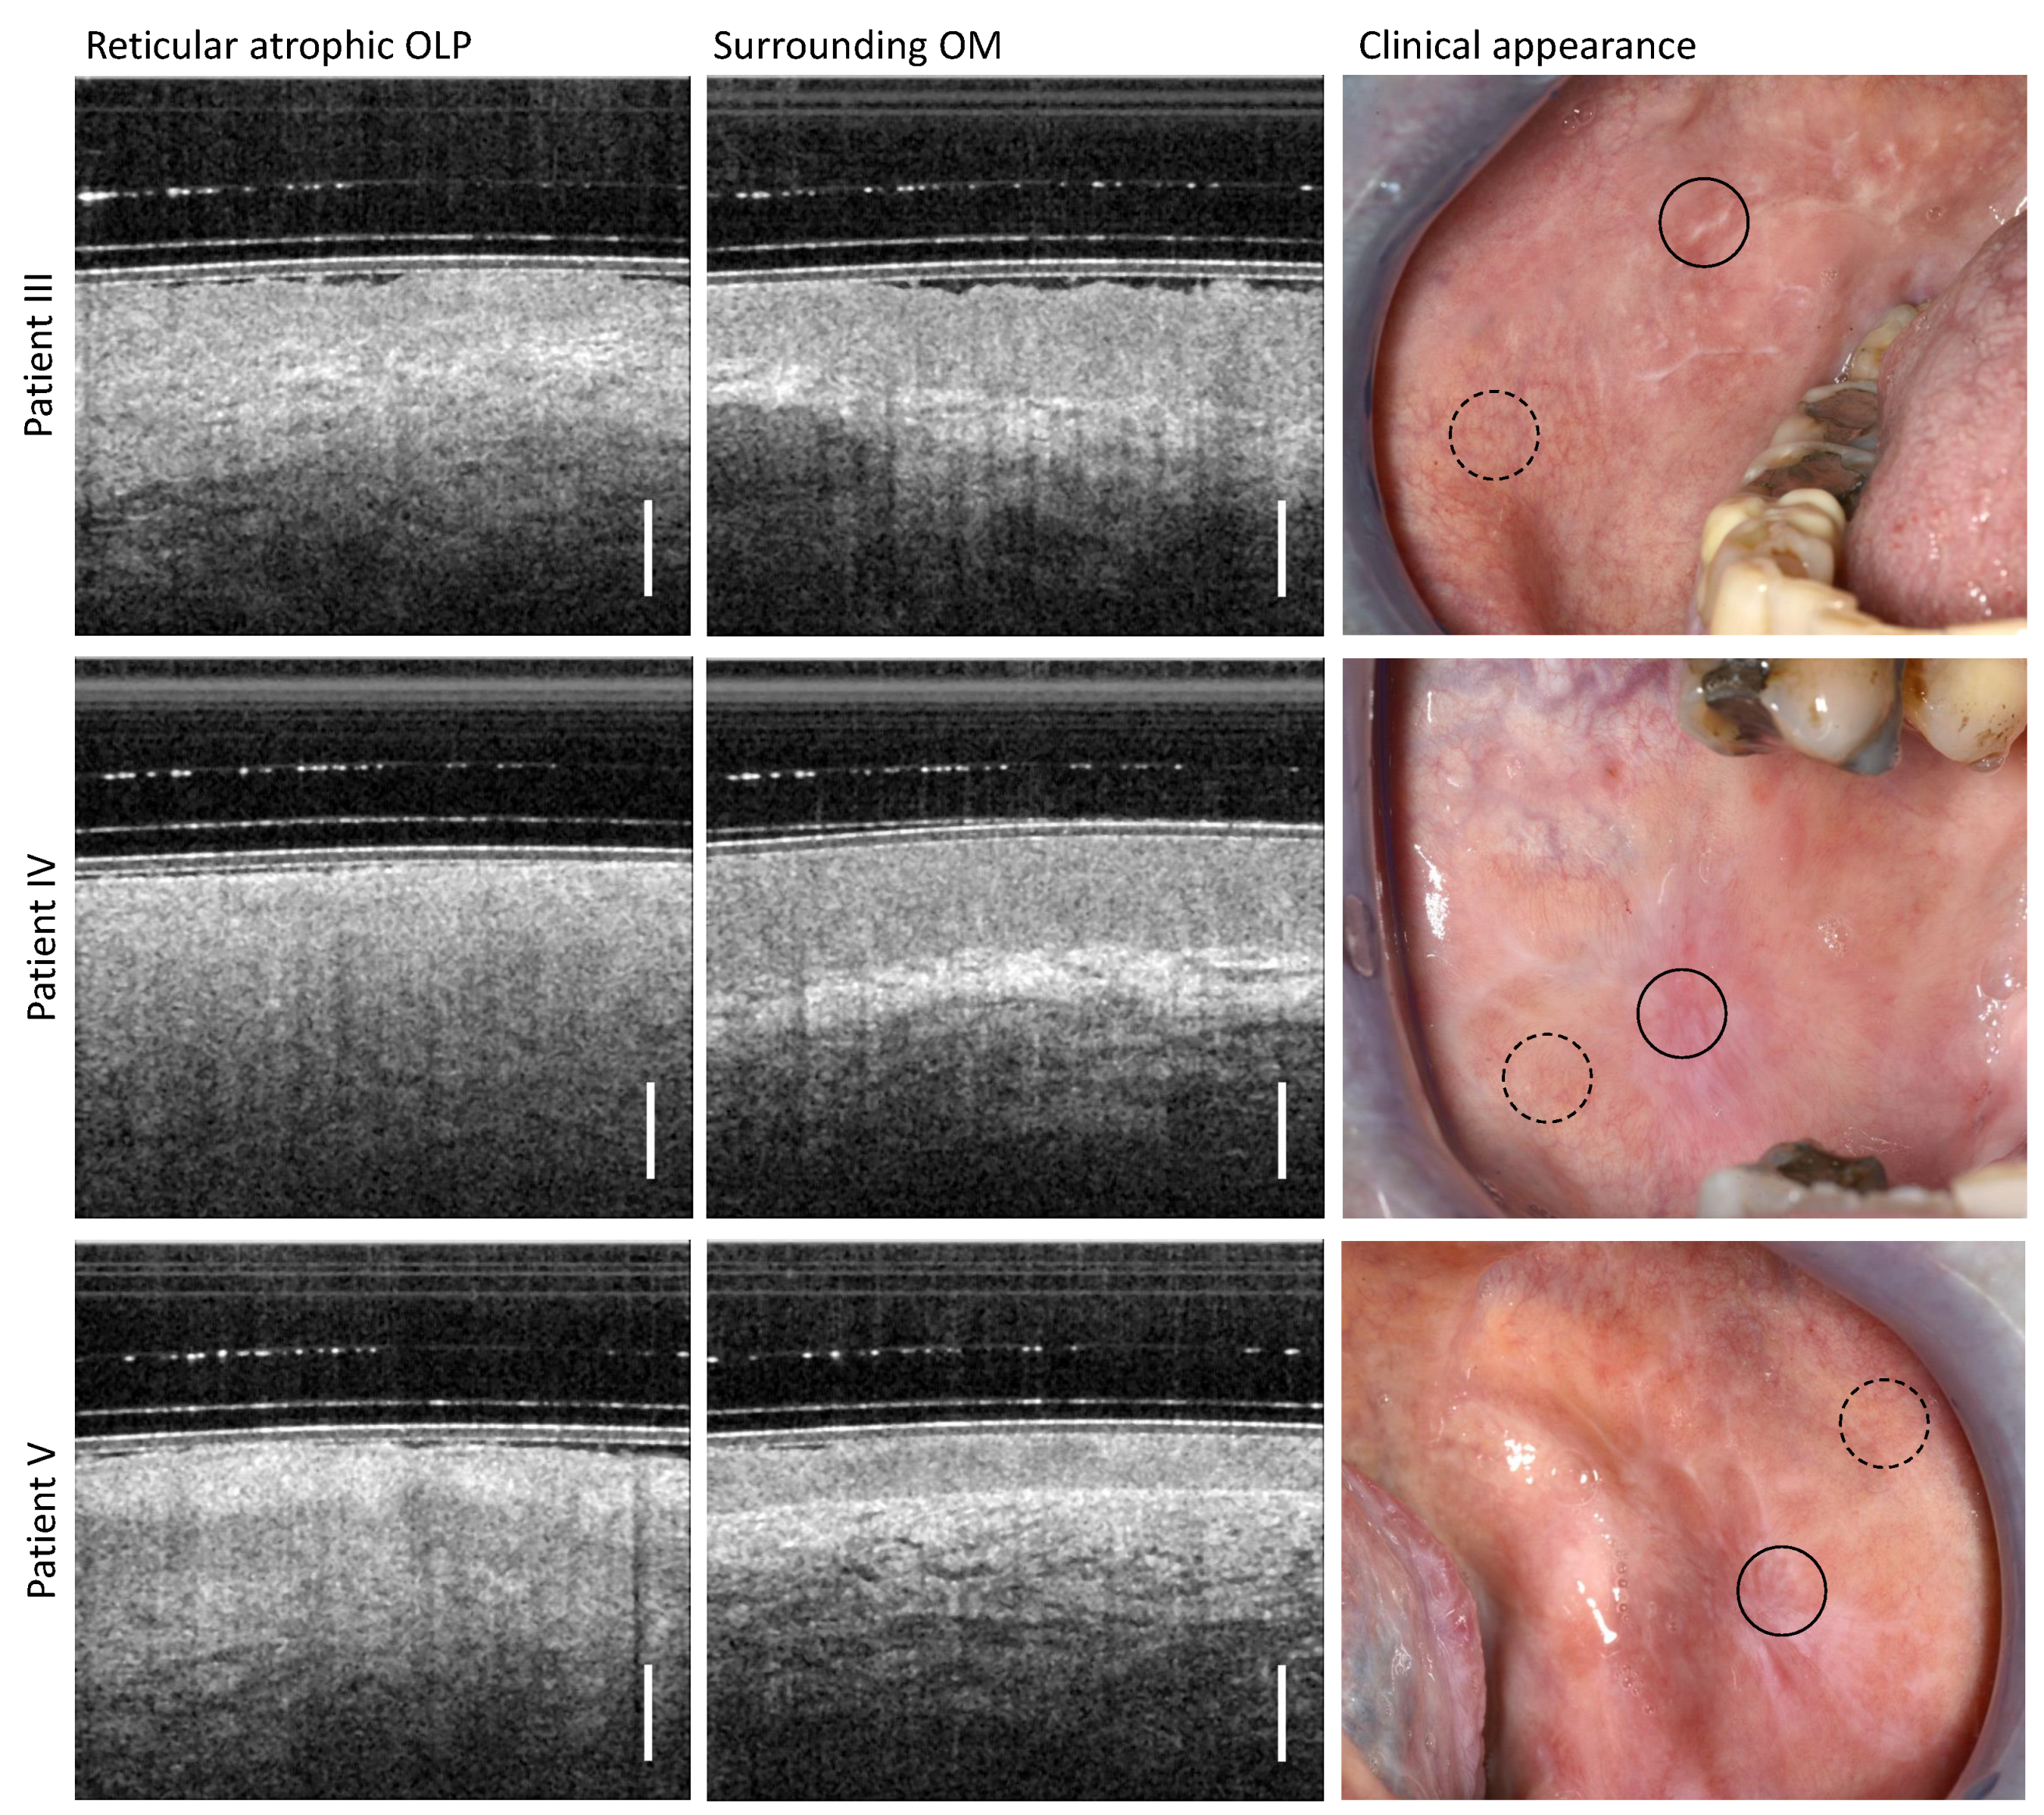

3.2. Reticular Atrophic OLP

| Reticular atrophic OLP | EP surface hyperreflectivity | |

| inhomogeneous OM surface | reduced EP thickness | |

| whitish reticular keratinization | reduced LP reflectivity | |

| marginal reddened surface | vague BM visibility | |

| reduced layer differentiation | ||

| reduced nb. of large vessels | ||

| III | male | 77 | OLP: right buccal mucosa; hypertension; unusual bleeding or bruising; osteoporosis; asthma; COPD; birch allergy; immunodeficiency because of the prostate cancer irradiation (2011); gallbladder operation | Antihypertensive drugs; Pantoprazol |

| IV | male | 80 | OLP: right buccal mucosa; hypertension | Antihypertensive drugs; Celestone Liquidum 0.5 mg/mL N1 (glucocorticoid drug) |

| V | female | 52 | OLP: left buccal mucosa hypertension; allergy to benzoyl peroxide, adhesives, ceramic restorations, perfume fragrances | antihypertensive drug-VIACORAM 7 mg/5 mg; Celestone Liquidum 0.5 mg/mL N1 (glucocorticoid drug) |